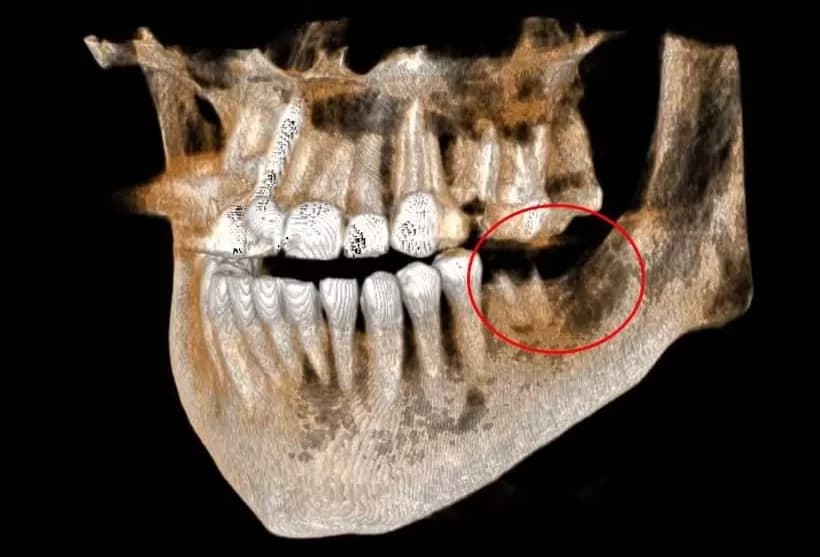

Advanced 3D cone beam imaging that creates detailed cross-sectional views of teeth, soft tissues, nerve pathways, and bone for complex procedures like implants and oral surgery.